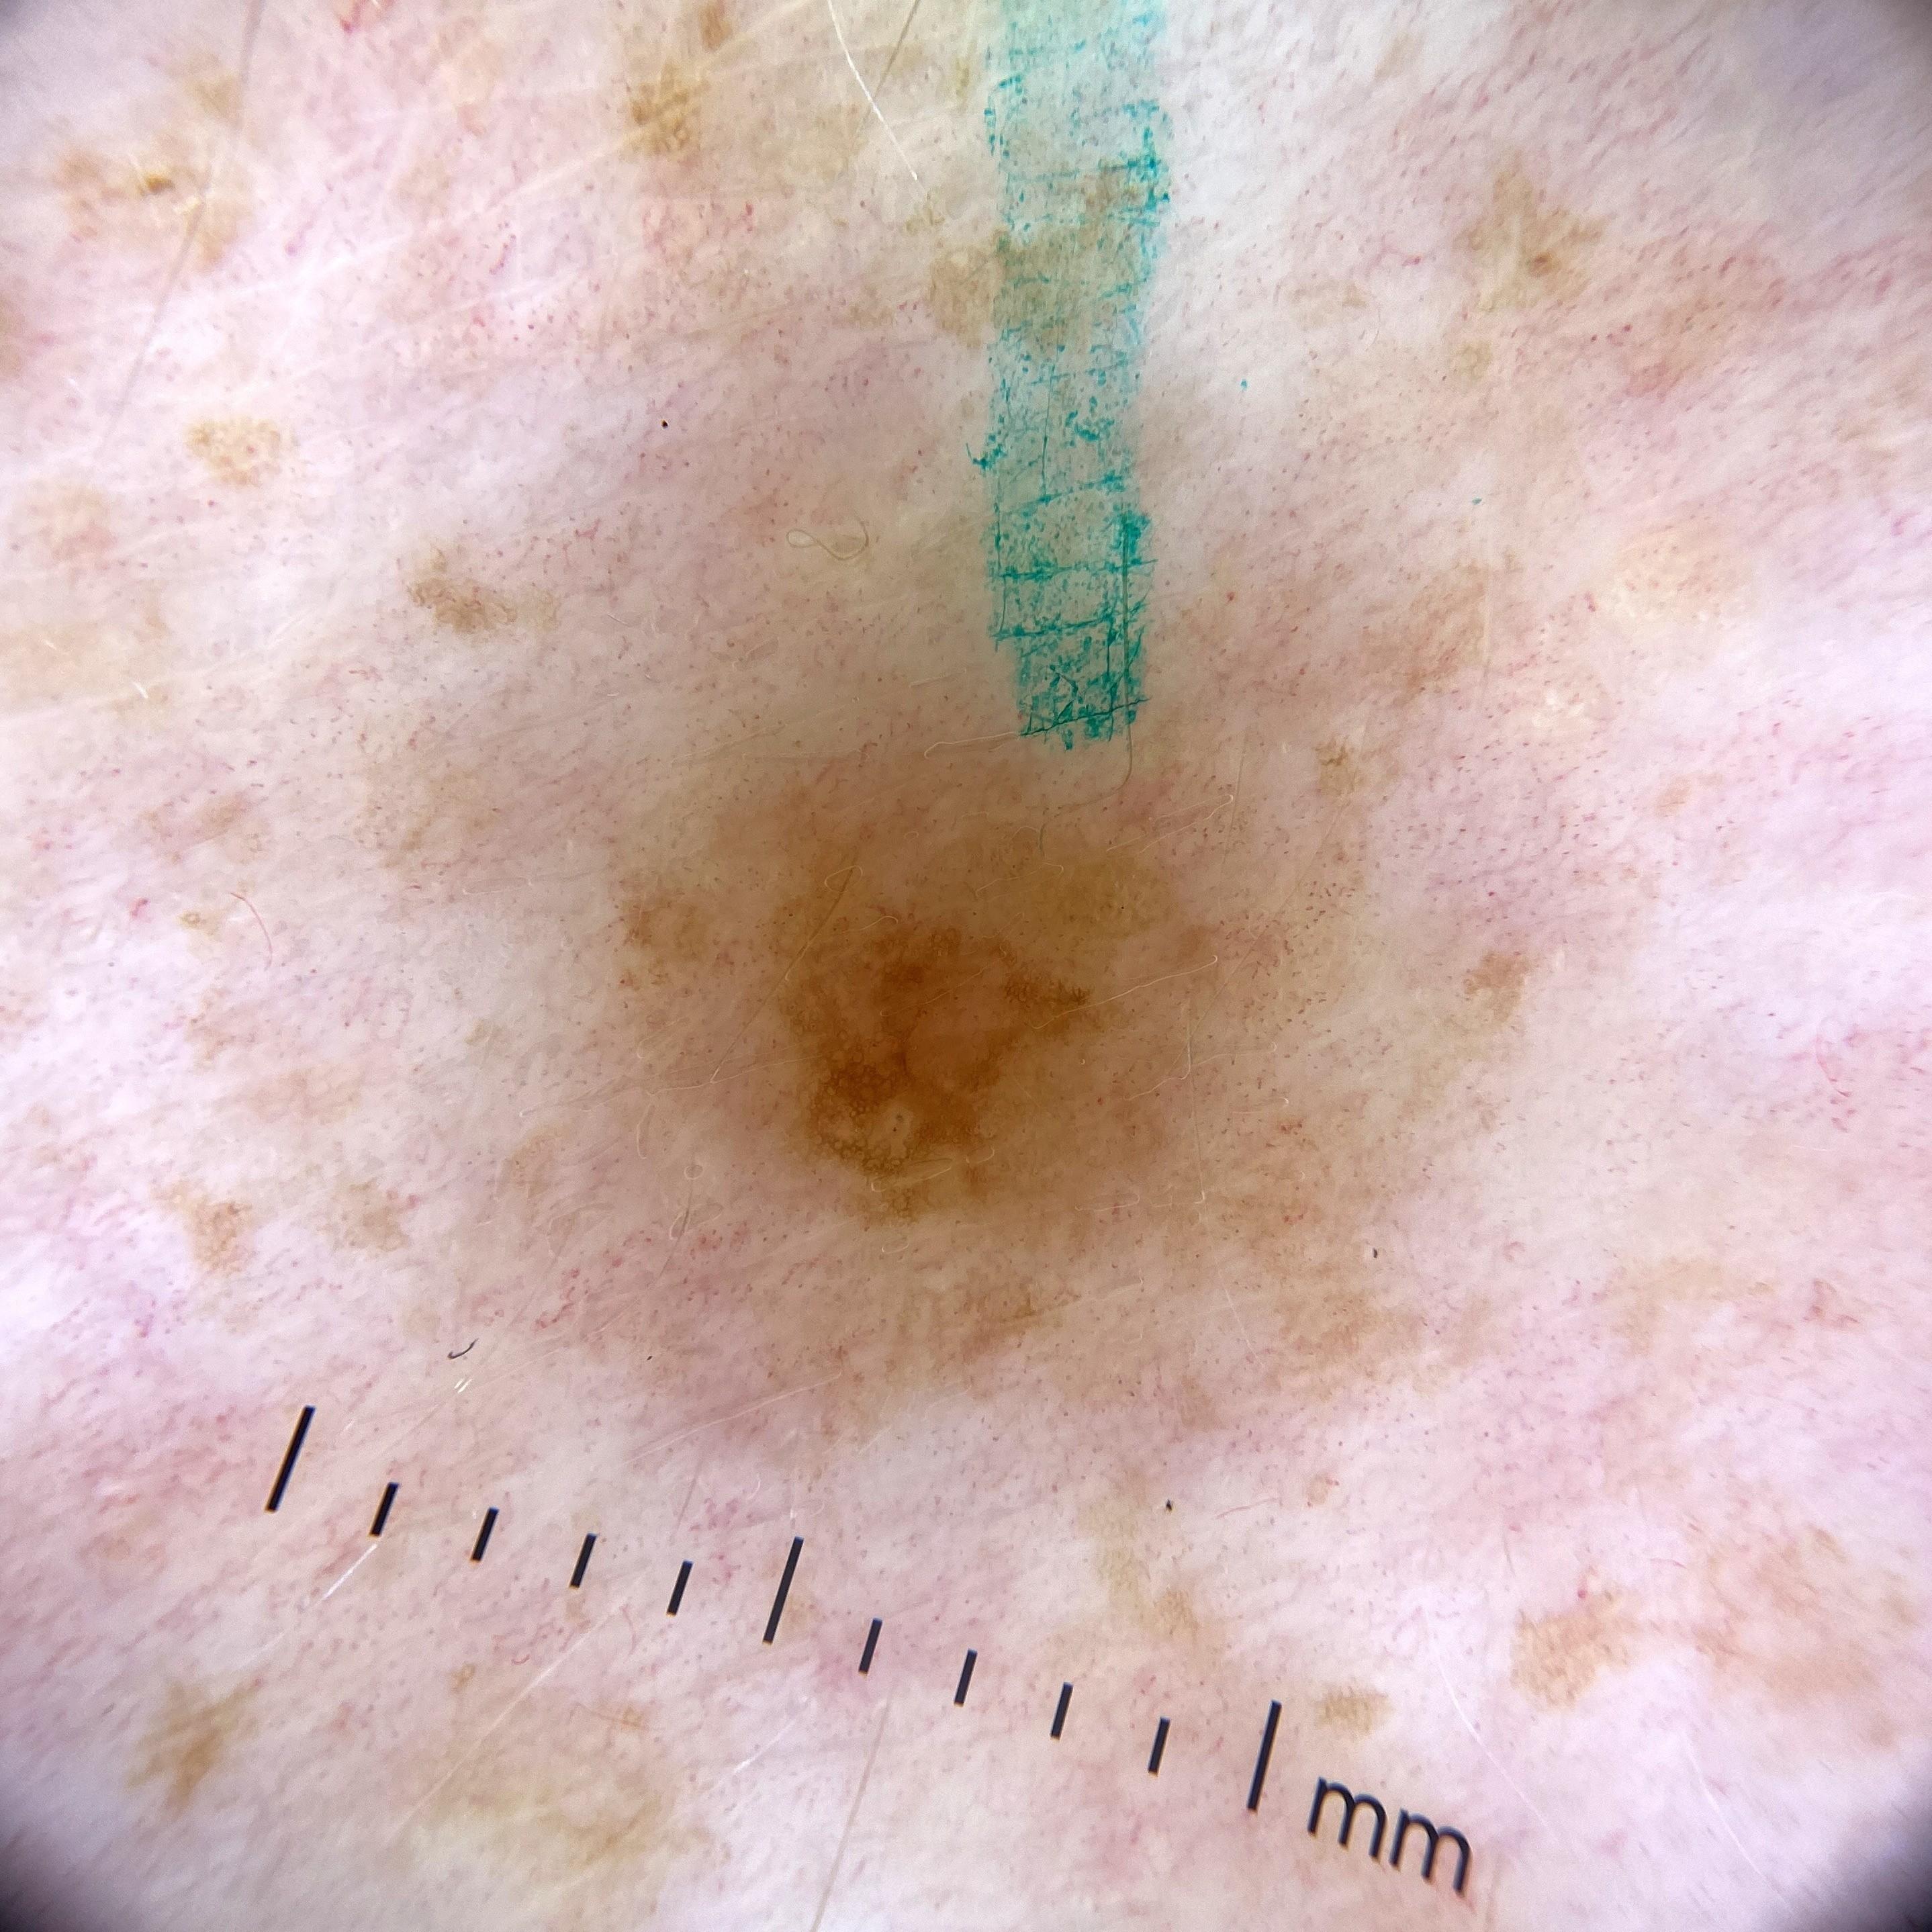

ISIC_3060871

2487 x 2487

Clinical

Field Value

acquisition_day 151

age_approx 55

anatom_site_1 Lower extremity

anatom_site_general lower extremity

diagnosis_1 Benign

diagnosis_confirm_type single image expert consensus

image_type dermoscopic

personal_hx_mm True

sex female